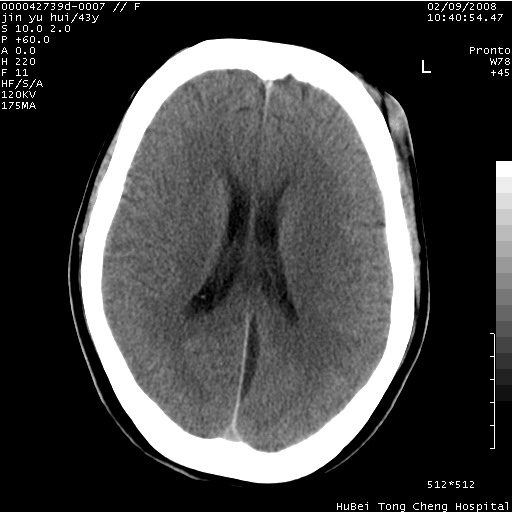

患者 女,43岁。头部外伤26天,经住院治疗,现头痛减轻。申请ct复查,了解颅内情况。

临床诊断:2级脑外伤。

颅脑ct轴位平扫(层厚、层距均为10mm),图像如下:

伴硬膜下水瘤

纵裂旁硬膜下水瘤,左额部头皮肿胀

大脑镰左旁硬膜下血肿慢性期。

大脑镰左旁慢性硬膜下血肿.

大脑镰左旁慢性硬膜下血肿.左额部头皮血肿.

是不是应该为:大脑镰左旁硬膜下血肿吸收期更妥当些;